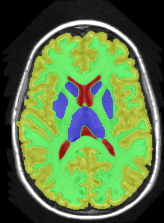

| ground truth | a-exp[7, 8] | QPBO [25, 8] | ours |

We extend [8], which introduced HINTS for arbitrary trees. In [8] a-expansion (a-exp) [7] was used to optimize the multi-label formulation of HINTS, but it often results in bad local minima due to complexities of interaction constraints, e.g. Fig.2. The contribution of [8] is a binary multi-layered HINTS formulation. They use high-order data terms, which are not easy to convert into unary and pairwise potentials for arbitrary trees. Their algorithm’s global optimality guarantee depends on the tree at hand. Only trees that do not yield frustrated cycles [25] have this guarantee, but this is not immediately obvious for any given tree. In [8], non-submodular binary energy implied by frustrated cycles were addressed by QPBO [25]. In practice, QPBO produces only partial solutions for most trees, see Figs. 2, 15 and 17.

3 Optimization

In Section 3.1 we introduce our Path-Move algorithm and in Section 3.2 we show which interaction constraints Path-Move could optimize. The authors in [8] showed that HINTS is non-submodular for a general tree and they used either QPBO or a-exp for optimization. Unfortunately, QPBO does not guarantee to label all pixels and we observed that in our experiments, see Fig. 2. The a-exp algorithm [7] is guaranteed to label all pixels but prone to weak local minima, Fig. 2.